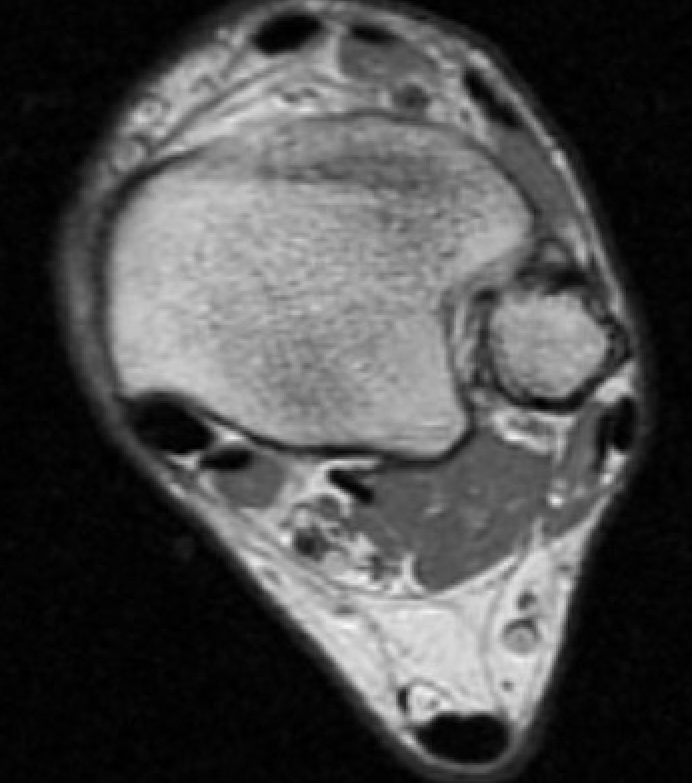

MRI

Tendonitis - fluid around tendon

Tendinopathy - tendon thickening

Tears

Tibialis posterior tendonitis

Tibialis posterior tendinopathy